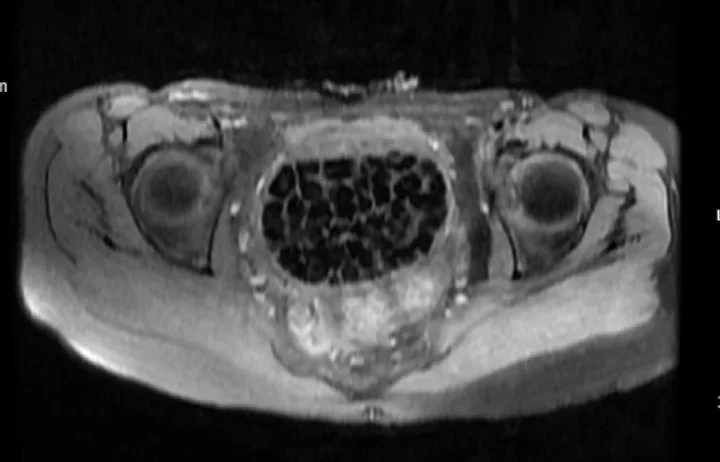

Hastasının durumuna yönelik konuşan Üroloji Uzmanı Doç. Dr. Erkan Erkan, "Hastamızın 2004 yılında doğduğunu ardından doğar doğmaz ekstrofi vezika dediğimiz 50 binde bir görülen bir anomaliden dolayı art arda ameliyatlar geçirdiğini öğrendik. 10 yaşında yine bir ameliyat geçirmişti, gerekli görüntüleme ve tetkiklerimizi yaptırdık. Normalde mesanesinin olması gereken yerin hemen arka kısmında taşlarla dolu bir kese olduğunu gördük, bunun üzerine ek görüntülemeler; MR çektirdik. Hastamız çelişkili açıklamalar almıştı, kendi radyolojik kliniğimiz ve edindiğimiz konsültasyonlarda taşların mesanede değil vajinal boşlukta oluştuğunu düşündük, bir planlama yaptık.

Kadın doğum hocamızın da çabasıyla taşları tamamen temizledik ardından ileride normal bir hayat sürmesi bakımından oraya plastik cerrahi yaptık. 287 adet taş çıkardık, pratikte gerçekten görünce çok şaşırdık çünkü bu aynı zamanda literatürde çok nadir görülen bir olay. Biz ameliyata hazırlanırken de teorik olarak biraz araştırdık. Literatürde gördüğümüz kadarıyla buna benzer bu tanıma uyan bir vaka vardı. Literatürde sanırım yayınlanmış 2’nci vaka olacak. Farkındalık çok önemli, bilinçli bir hastamız vardı. Doğumsal anomaliyle doğan çocuklarımızda ileride bunlara bağlı bazı sıkıntılar çıkabileceğinin öngörülmesi lazım. İlgili tedavilerini alsalar bile düzenli takiplere gelmeleri gerekiyor. İleride eğer dikkat etmezse ki zannetmiyorum, tekrarlayabilir. Bu rahatsızlık ekstrofi vezikal epispadias durumu çok nadir bir durum" dedi.

Genç kızın uzun süredir devam eden karın ağrısı olduğunu söyleyerek sözlerine başlayan Jinekolojik Onkoloji Uzmanı Op. Dr. Emin Erhan Dönmez, "Mesane taşları olduğu düşünülerek daha büyük bir hastaneye refere edilmiş. Aramızda mini bir konsey yaparak muayene ettik. Vajen bir hazne görevi görerek orada durağan bir idrar, uzun süre beklediği için idrar içindeki minerallerde çökerek taşlar oluşmuş. Mesanedeki idrarın vajene akmış olabileceği ve vajende göllenen idrar nedeniyle taşların burada oluşacağını düşündük, ameliyatımızı planladık. Ameliyata tanı amaçlı girmiştik, sistoskopi (Mesane gibi idrar yollarını kapsayan kısımlardaki rahatsızlıkların teşhis ve tedavisinde kullanılan endoskopik bir yöntem) dediğimiz ameliyatı Erkan Hocam ile birlikte gerçekleştirdik.

Önce mesaneyi bir görüntüledik, mesane tabanına yaklaşık 2-3 cm’lik bir alandan vajene fistülize olduğunu gördük. Mesaneden vajene geçtiğimiz esnada tüm vajenin taşlarla dolu olduğunu gördük. Tanı amacıyla girdiğimiz ameliyatta her şey de olağan gittiği için tedaviye geçtik. Taşların çıkabileceği kadar bir genişlik sağladık. Daha sonra yaklaşık en büyüğü 2,5 cm boyutlarında olan, irili ufaklı 287 tane taşı ameliyat esnasında çıkarmış olduk. Taşların tekrarlamaması için idrarın göllenmemesi, en azından dışarıya rahatça boşalabilmesi için vajinal rekonstrüksiyonu sağladık. Ameliyatta da herhangi bir problem yaşamadık. Literatürü Erkan Hocam ile birlikte değerlendirmiştik. Primer olarak vajende birikmiş olan bu kadar çok sayıda taşla ilgili bir makale görmedik, rastlamadık" dedi.